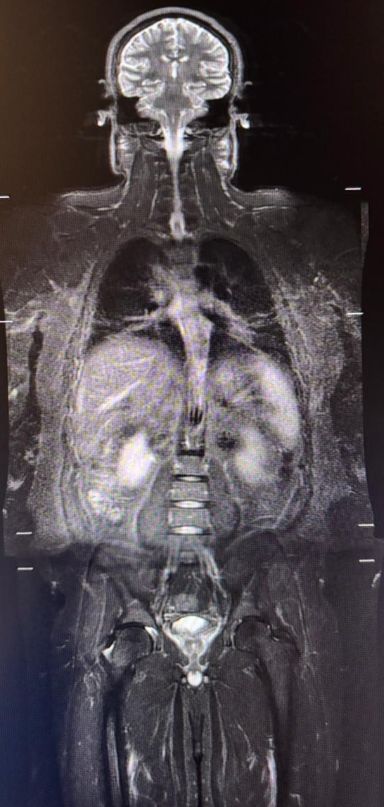

Ressonância magnética de corpo inteiro

A ressonância magnética de corpo inteiro (RM de corpo inteiro, ou WB-MRI) se consolidou como uma das ferramentas mais relevantes da imagem oncológica moderna. Trata-se de um método sem radiação ionizante, com excelente contraste tecidual e grande sensibilidade para detectar doença em múltiplos segmentos do corpo. No entanto, embora o nome do exame seja o mesmo, seu papel muda de forma importante conforme a indicação clínica. Isso fica especialmente claro quando comparamos sua aplicação na hematologia, particularmente no mieloma múltiplo, com seu uso na oncologia de vigilância, como no rastreio de pacientes com síndrome de Li-Fraumeni.

Já na oncologia hereditária, especialmente na síndrome de Li-Fraumeni, o objetivo é diferente. Aqui, a RM de corpo inteiro entra como ferramenta de vigilância global, buscando tumores em fase inicial em diversos órgãos e tecidos, incluindo sarcomas ósseos, sarcomas de partes moles e neoplasias viscerais. As recomendações atuais mantêm a RM de corpo inteiro anual como componente central do programa de rastreamento desses pacientes, em geral associada também à RM de encéfalo anual.

Na oncologia, sobretudo nos programas de rastreio de pacientes de alto risco, como os portadores de síndrome de Li-Fraumeni, a RM de corpo inteiro funciona como uma estratégia de detecção precoce de tumores sólidos. O raciocínio deixa de ser centrado na medula e passa a ser global, incluindo ossos, partes moles, abdome, pelve e outros órgãos.

Nessa aplicação, a RM de corpo inteiro costuma privilegiar uma leitura anatômica ampla, em busca de massas suspeitas, assimetrias, lesões agressivas e alterações que justifiquem investigação dirigida. Muitos centros utilizam protocolos com T1 e STIR de corpo inteiro, frequentemente associados à difusão, mas a lógica não é a de quantificar infiltração medular, e sim a de ampliar a sensibilidade do rastreamento global. Em várias séries contemporâneas de vigilância em Li-Fraumeni, o exame é realizado sem contraste e de forma periódica, justamente para permitir seguimento longitudinal seguro e repetido.